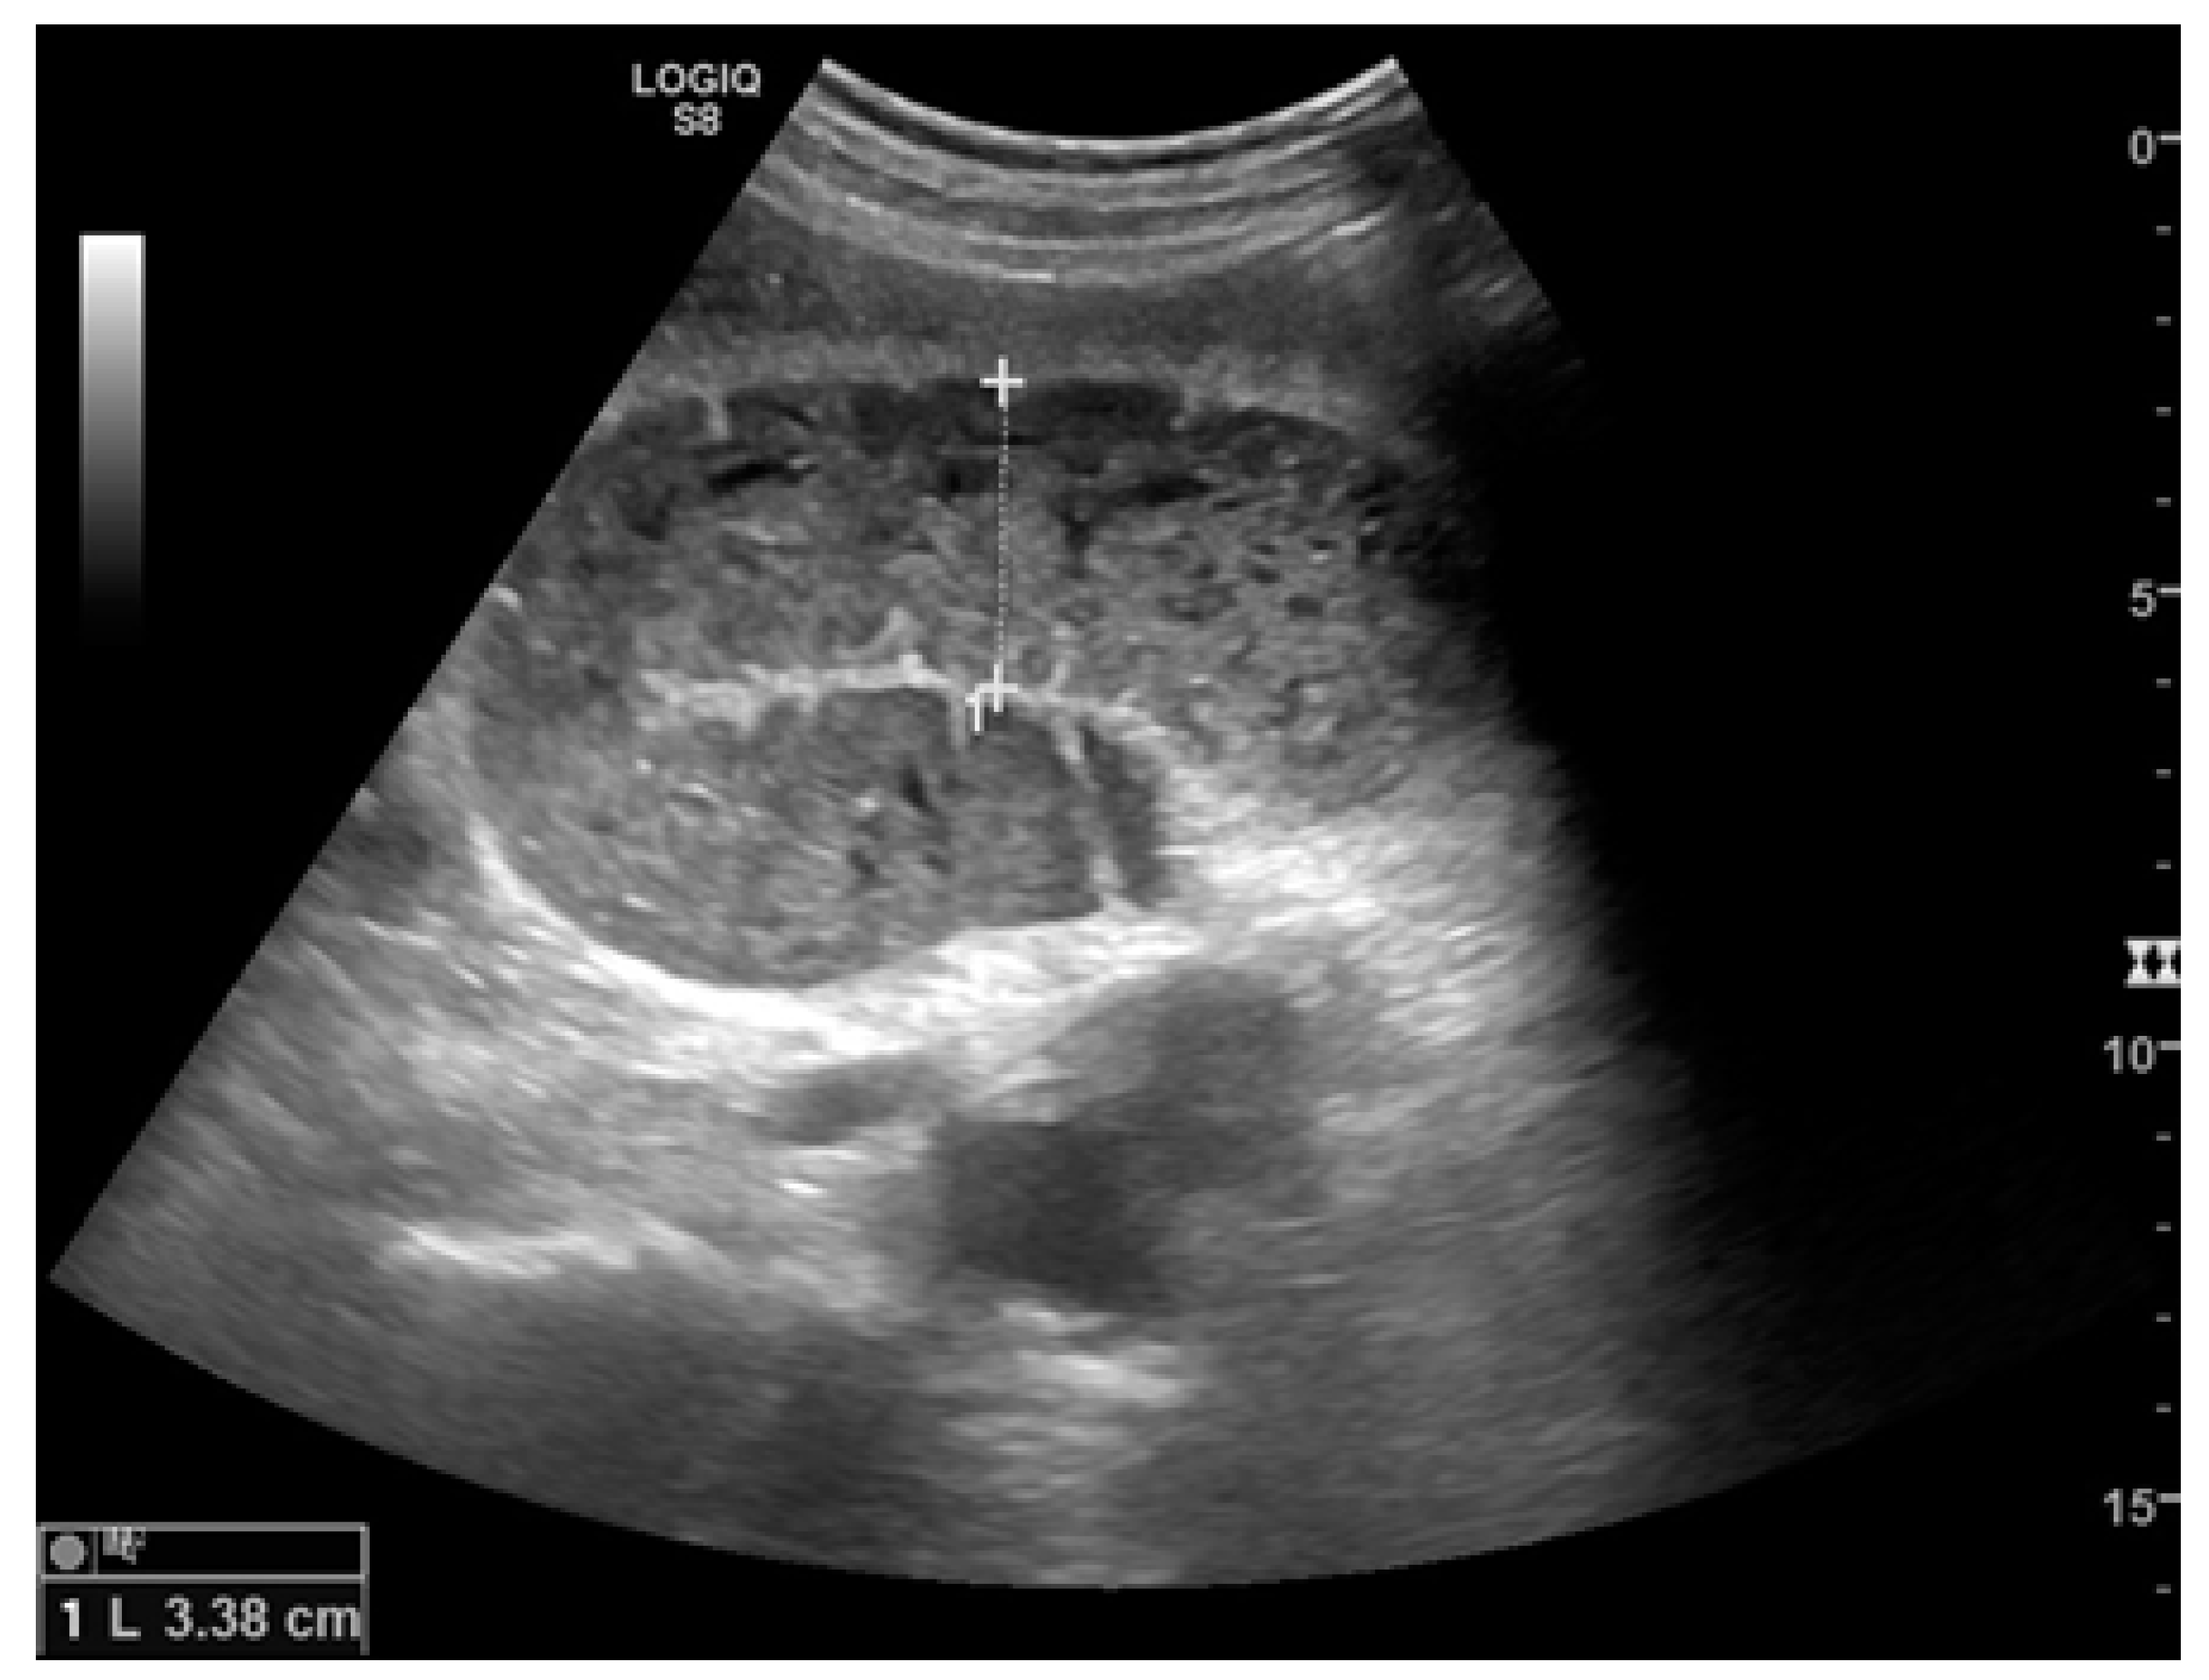

Figure 4.

A complicated SBO in a 69-year-old male with gastric cancer and peritoneal carcinosis. Ultrasound images show long (a) and axial (b) evaluations of a fluid-filled, dilated small bowel loop with hyperechogenic floating material (shown with an asterisk) (b,d). Bowel peristalsis was absent. Mild parietal and valvulae conniventes thickening are present (c,d). Downstream loops present normal caliber (bowel jump diameter). Free fluid is interposed between bowel loops (black arrow) (b).